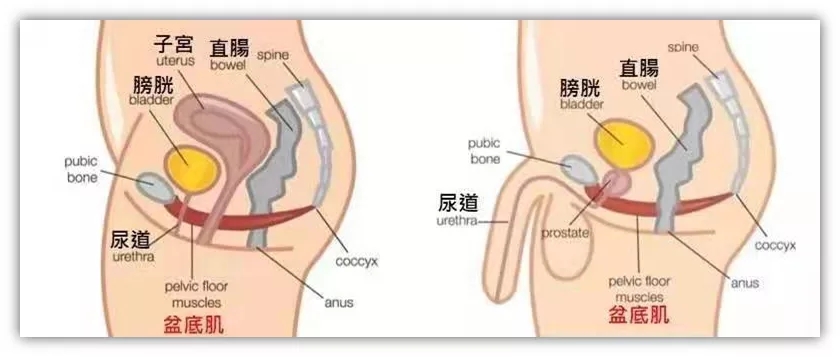

你对盆底肌(PC肌)了解多少?

很多人可能都没有听说过,但这一部分肌肉群你一定每天都在用。

什么是盆底肌?

盆底肌是指封闭骨盆底的这一部分肌肉群。它像一张吊网一样托着我们的尿道、膀胱、直肠、阴道、子宫、前列腺等脏器。使这些脏器维持其正常的位置,良好的行使其功能。

女性盆底肌群大致分为三个部分:肛门附近的括约肌、阴道附近肌肉群以及控制尿道的肌肉群。